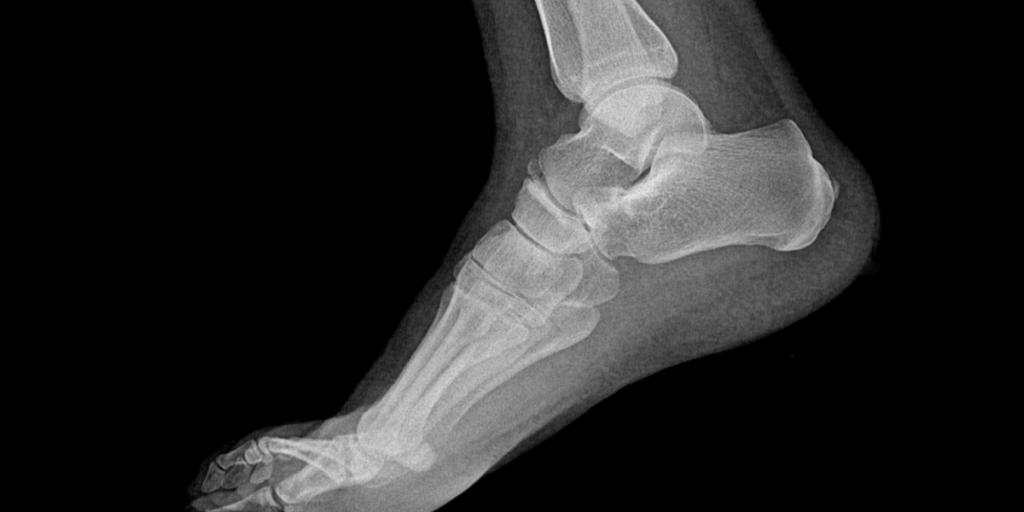

Esta condición se caracteriza por una prominencia ósea en la parte posterior del calcáneo, el hueso que forma el talón. Esta protuberancia puede causar fricción e irritación en los tejidos blandos circundantes, como el tendón de Aquiles y la bolsa serosa, lo que resulta en dolor y molestias al caminar o al realizar actividades que involucran el movimiento del pie.